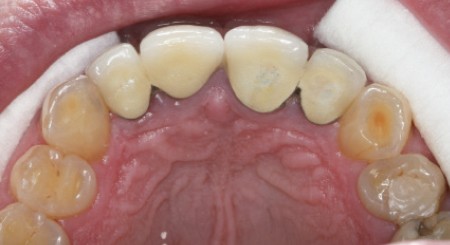

Dents : soins dentaires à réaliser sur 16, 26, 37.

Amputation mésiale de 46 ?, légères érosions.

Bruxisme : net avec attrition antérieure marquée en particulier en regard des coiffes céramiques.

Occlusion : décentrage gauche, création d’une légère béance antérieure probable conséquence

de l’atteinte de l’ATM gauche.